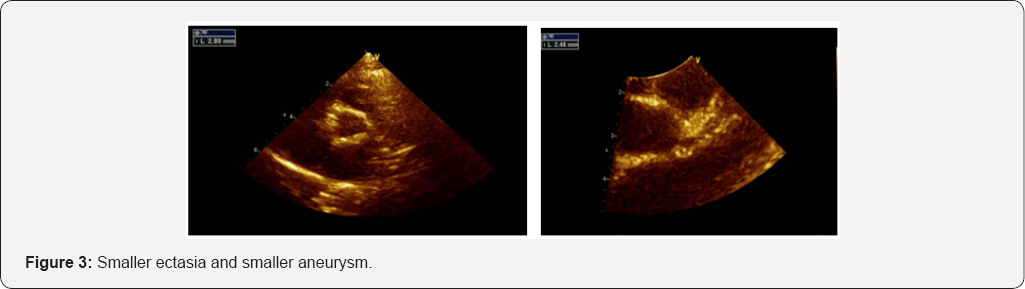

Her echo findings showed: Both coronary arteries looks smaller than before with ectasia along the course of both coronary LCA 2.2mm, LAD 2.6mm [14]. Small aneurismal formation measuring 2.9mm at the origin of RCA distal RCA is normal 2mm (Figure 3).